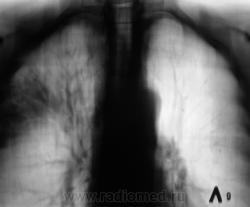

Произведена рентгенограмма в прямой стандартной проекции и томограммы в стандартных срезах.

«Пневмония», сразу показалась какой-то «фердиперсовой», с учетом лечения в стационаре ранее, довольно хорошего самочувствия пациента и наличием весьма «убогой» клиники. После проведения исследования было рекомендовано провести противовоспалительное лечение, исследование мокроты с целью проведения дифференциальной диагностики, рекомендована консультация фтизиатра.

Мы в протоколе, конечно, отметили, о возможности инфильтративного туберкулёза, д/д ряд даже не дали.

Пациент 4 месяца, по полной программе отлежал в областной конторе, ЦВК утвердило «инфильтративный». После выписки был направлен под надзор фтизиатра по месту жительства. Ниже иллюстрации после выписки.

Снимки сегодня.